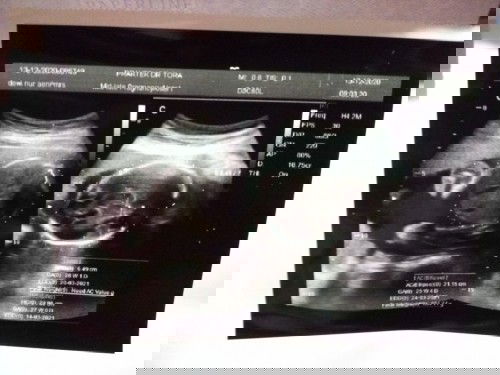

Usg 2Dimensi

Hasil USG kemarin usia kandungan menurut hpht 25week5day, hasil usg 26week1d. Hpl hpht 23 maret, hpl usg 20 maret, Bbj udh 884.77gr Jk insyaallah perempuan, Tapi posisi masih lintang mudah2an kedepannya bisa normal semua dan dipermudah proses kelahiran nya 😍😍😇😇